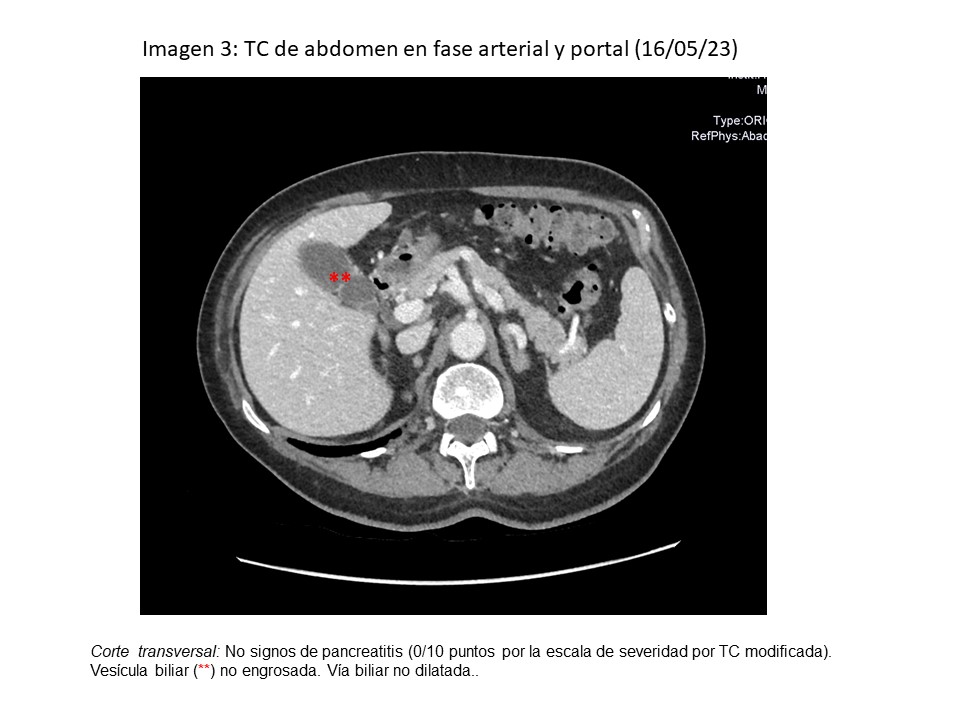

• TC abdomen en fase arterial-portal (16/05): normal.